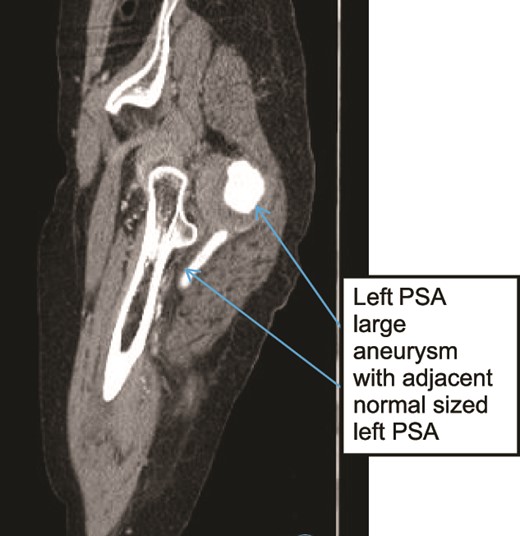

Case 3—sagittal images of LL CTA of the left LL arteries showing large aneurysm with surrounding thrombus with adjacent patent normal sized upper left PSA.